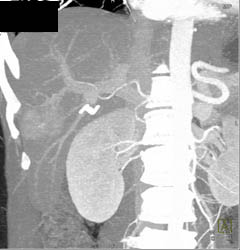

Celiac and Hepatic Artery Aneurysms in Multiple Phases